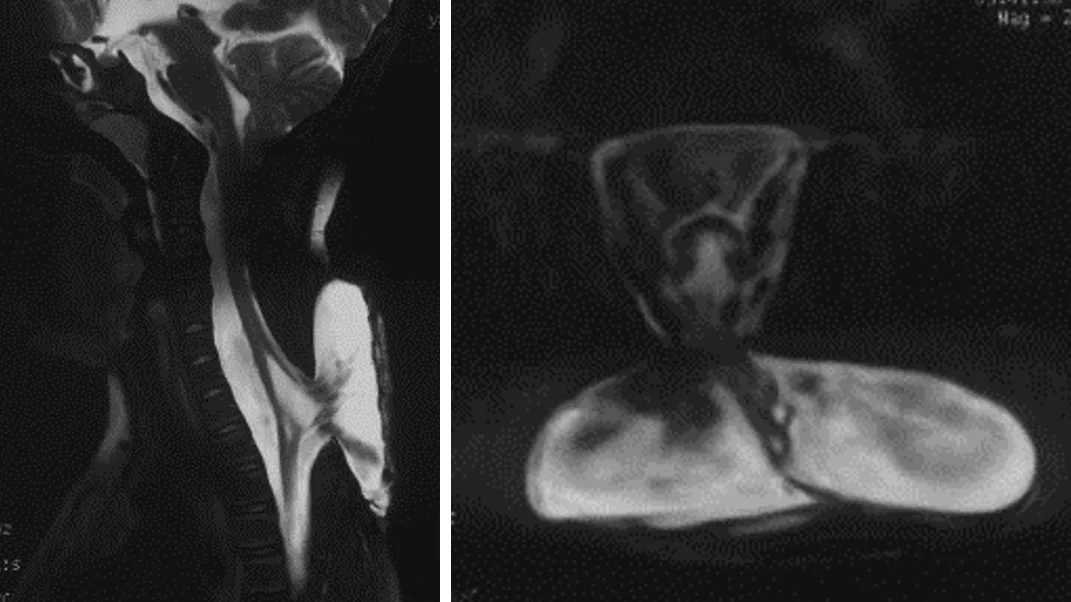

Preoperative MRI images show that the nerves have been pulled out of the spinal canal with the cystic hernia

After admission, Dr. Duan arranged a series of examinations and assessments for Yang Yang. Dr. Xing Tianying from the Department of Urology was invited to perform a detailed urodynamic examination to assess whether there was neurogenic lower urinary tract dysfunction. Technician Zhang Mo from the Department of Radiology completed a detailed imaging scan, which revealed the fine structure of the bulging spinal cord.

The child had defects in the vertebral plates of multiple segments, and the spinal cord structure in the cervical-thoracic junction area within the vertebral canal had been pulled backwards and deformed, with the nerve tissue adhering to the inner wall of the cyst's top. This part of the structure is part of the central nervous system, and if it is damaged during surgical separation, it could cause the child to experience numbness or paralysis in the limbs, or even more serious problems. Another difficulty of the operation is that the pulled spinal cord is separated from the outside world by only a thin layer of keratinized skin tissue at the top of the cyst. The spinal cord needs to be returned to the vertebral canal, the water environment surrounding the spinal cord needs to be reconstructed, and the muscles, subcutaneous tissue and skin need to be covered again.